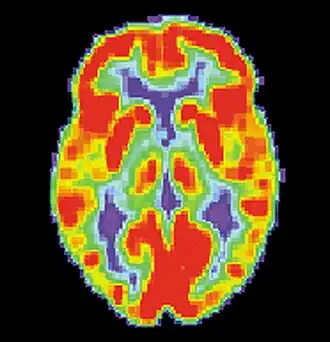

PET scan of a healthy brain - Image courtesy of US National Institute on Aging Alzheimer's Disease Education and Referral Center -

PET scan of brain with AD - Image courtesy of US National Institute on Aging Alzheimer's Disease Education and Referral Center